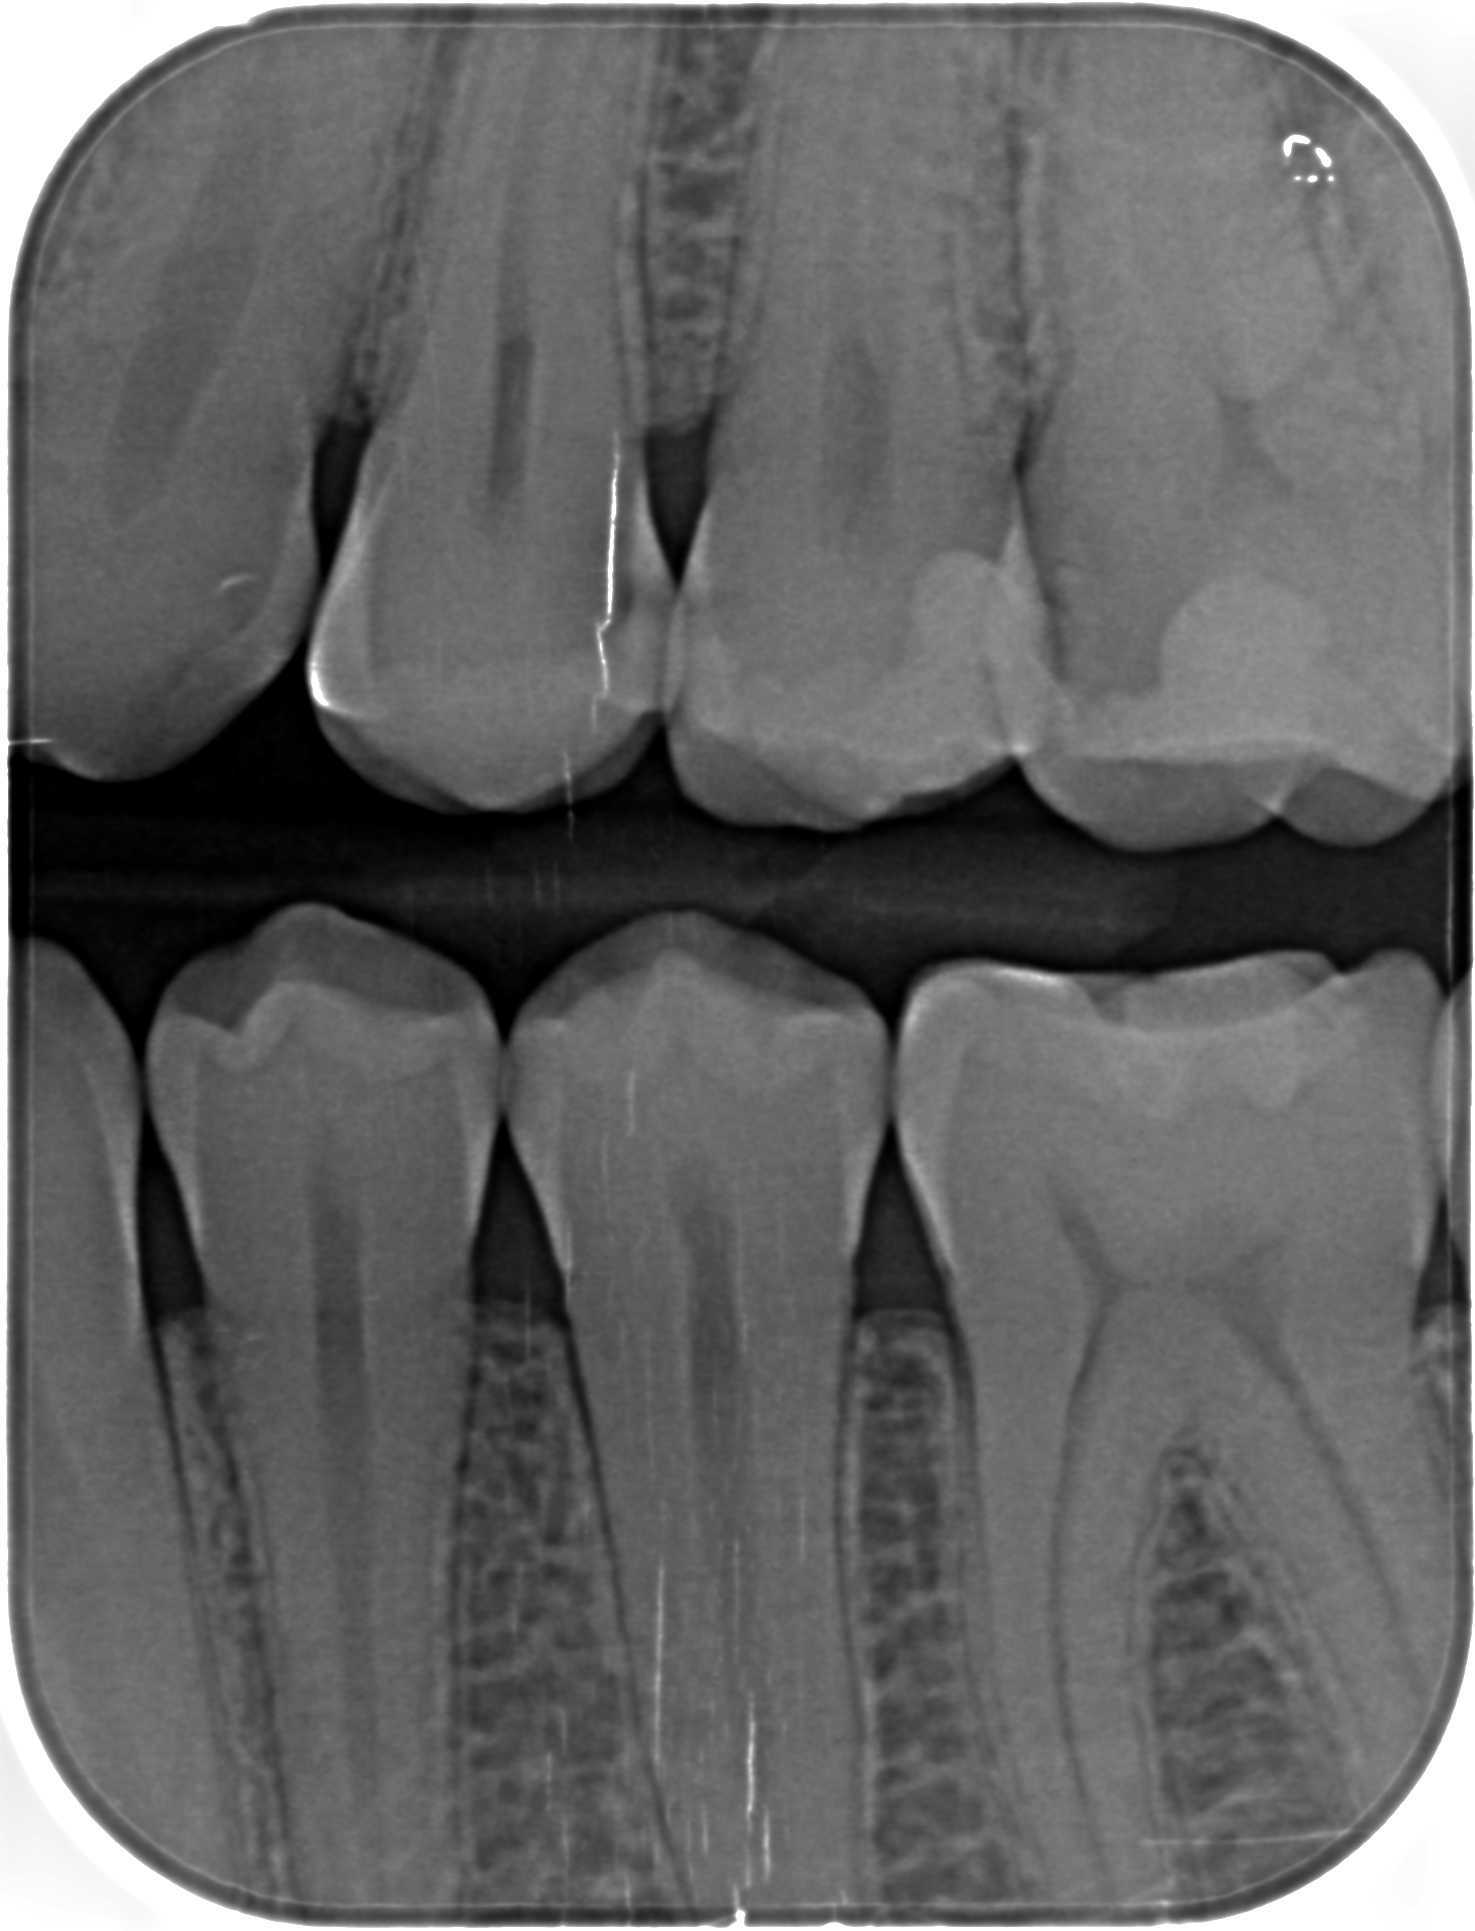

ho fatto una visita dal dentista dove ad occhio nudo ha visto qualche carie e ha poi pensato di fare le lastrine che ho riportato sotto, dove ci vede 7 carie.

Ho fatto poi una seconda visita da un altro dentista dove ad occhio nudo non ha visto niente (strano perchè le igeniste dentali vedevano una carie) ma nelle lastrine ha visto 5 carie

mi potete dire quante carie ci vedete voi e se sono negli stessi denti indicati negli schemi allegati?